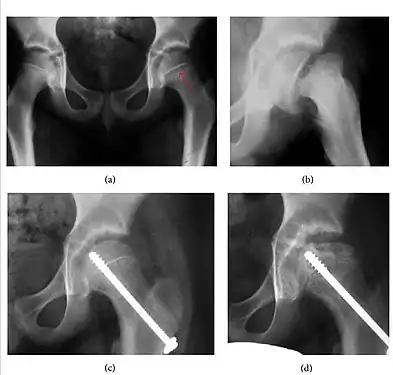

Slipped capital femoral epiphyses (SCFE) usually affect 11- to 14-year-old adolescents (Figure 4). Radiographs may show widening and irregularity of the physis and posterior inferior displacement of the capital femoral epiphysis. On the AP view Klein’s line, tangent to the lateral aspect of the femoral neck, does not intersect the femoral head indicating that it is displaced. SCFE may compromise the blood supply to the femoral head and cause avascular necrosis, mainly when there is instability between the fragments.[1]

Figure 4: (a) X-ray of a 10-year-old child with left hip pain. It was considered normal at emergency despite the widening of the left physis (arrow). Two weeks later epiphysiolysis was evident (b). Despite appropriate surgical reduction (c) osteonecrosis developed and femoral head collapsed 1 month later (d).[1]